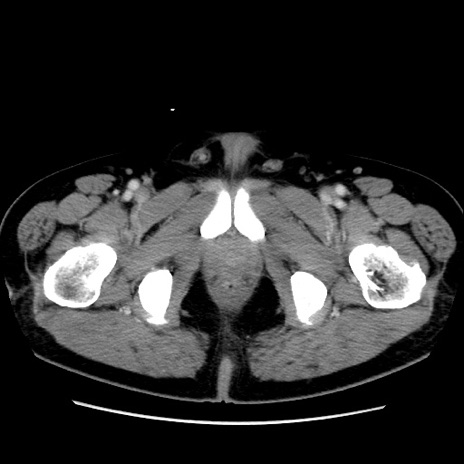

症例16(横断像)

【現病歴】 約1ヶ月前より間欠的に腹痛と嘔吐あり、当院消化器内科を受診したところCTで多発する肝臓のLDAを指摘され、精査中であった。以降は消化器症状は安定していたが、2日前より嘔気と腹痛があり、同日より排便・排ガスが消失した。改善認めず、 本日、救急外来を受診した。